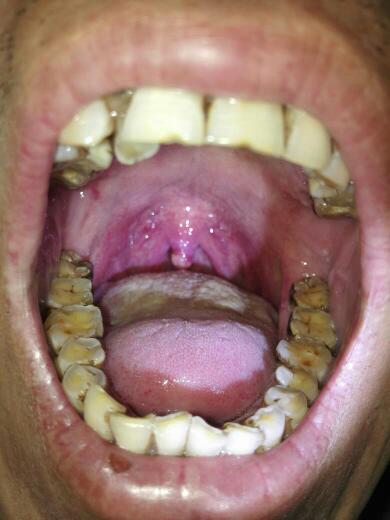

求救 求救求救 懂的医师 专家 麻烦耽误几分钟给我看一下 开始悬雍垂

这位患者(图2)咽充血,尤其是悬雍垂充血肿胀显著,双侧扁桃体均可见

男孩六周岁,镜下所见,悬雍垂水肿,咽部粘膜充血,咽后壁淋巴滤泡增生